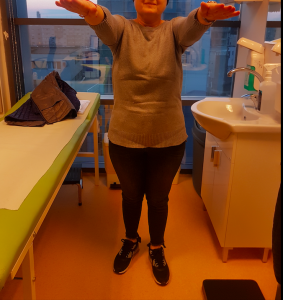

Doamna Toma și-a revenit imediat după ce efectul anesteziei a trecut. Aceasta a reușit să recupereze tulburările cu care se prezentase inițial la spital, după o zi petrecută la reanimare și alte patru zile de internare în cadrul secției de neuorchirugie. Examenele CT realizate după operație au indicat faptul că tumorăa a fost extirpată în totalitate, ceea ce confirmă faptul că operația a fost un real succes!

În cea de-a cincea zi, pacienta noastră, doamna Maria Toma, s-a întors acasă la familia sa, pe propriile picioarele și a revenit după alte 15 zile pentru control. Evoluția locală a fost una excelentă iar în prezent, doamna Toma a început un tratament oncologic de specialitate, urmând să revină la controale neurochirurgicale periodice.

Doamna Maria Toma este o persoană luptătoare, care s-a prezentat la medicul neurochirurg când și-a dat seama că există o problemă reală, care trebuie investigată. Dr. Dan Benția și întreaga echipă medicală îi urează multă forță și curaj pentru o însănătoșire grabnică!